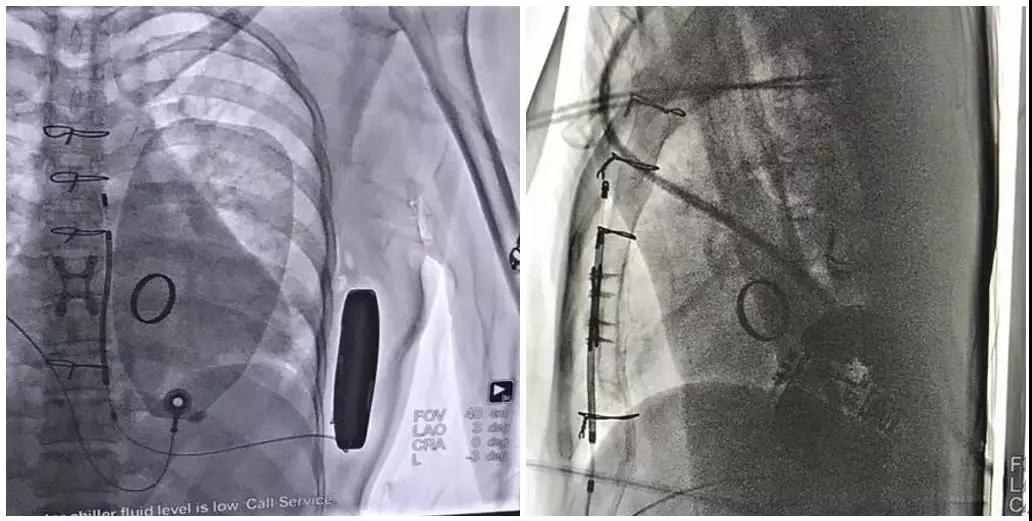

术后影像